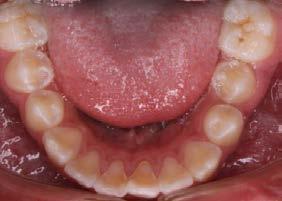

Figura 1. Fotografía oclusal.

derecho (Figura 1). Especialista en endodoncia solicita cone beam en donde se visualiza lesión periapical extensa que involucra segundo y tercer molar ipsilateral y engrosamiento de la mucosa del seno maxilar sugerente de sinusitis maxilar crónica y su cercanía

con el tercer molar de dicha estructura (Figura 2).